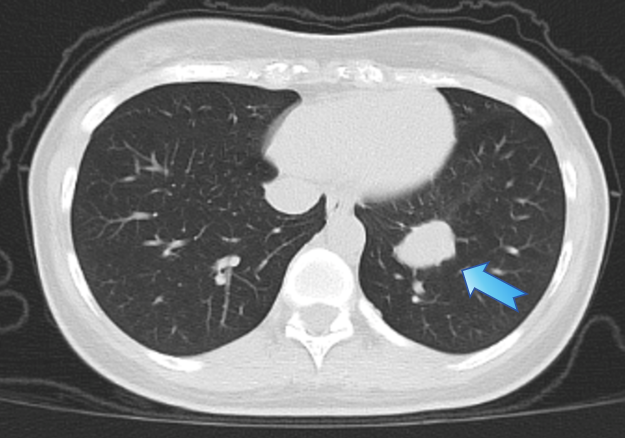

术后CTA复查:动脉瘤得到了精确且完全栓塞

术后第二天肺动脉CTA复查显示:动脉瘤被完全“封堵”,局部血流切断。王女士恢复平稳,未再出现咯血,随后顺利出院。她感慨道,感觉自己全好了!

在手术室和麻醉科的支持下,瑞金医院血管微创介入治疗团队为王女士实施介入手术:由王忠敏主任医师主刀、王子寅副主任及单群刚主治医师担任助手,从股静脉穿刺建立通道,在影像引导下将导管逐级送入左肺下叶病变分支,完成超选择性插管,造影清晰显示动脉瘤轮廓与供血。确认定位后,于瘤腔内精准释放多枚解脱弹簧圈,阻断瘤内血流。复查造影未见残余充盈,提示出血风险已被当场解除。整个过程不开胸、不切肺,体表仅有一个微小穿刺点。